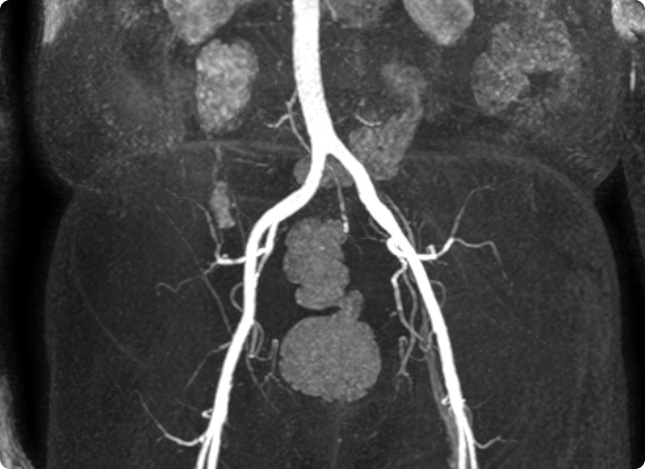

- Gefäßdarstellung